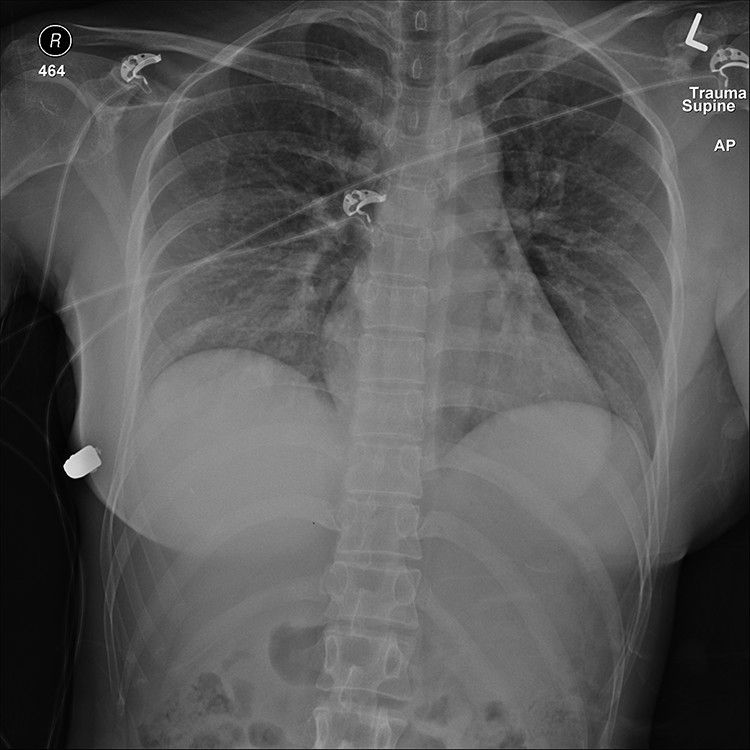

El equipo médico de un hospital local descubrió una herida de bala en la parte superior de su seno izquierdo. Las marcas de quemaduras alrededor de la herida indicaban que a la mujer le dispararon a corta distancia. La bala se alojó bajo su pecho derecho, habiendo entrado en el pecho izquierdo, fracturando una costilla en el proceso, antes de detenerse en el lado derecho de su cavidad torácica.

Las pruebas hechas después de la operación revelaron solo daño en el tejido pulmonar, y mostraron que la bala había pasado por ambos implantes.

Tras una reconstrucción de la trayectoria de la bala a través del pecho de la mujer, el equipo médico concluyó que habría impactado en su corazón de no ser por el implante izquierdo. "Este implante cubre el corazón y la cavidad intratorácica y por lo tanto probablemente salvó la vida de la mujer", afirmó el equipo de investigación dirigido por el cirujano plástico Giancarlo McEvenue.